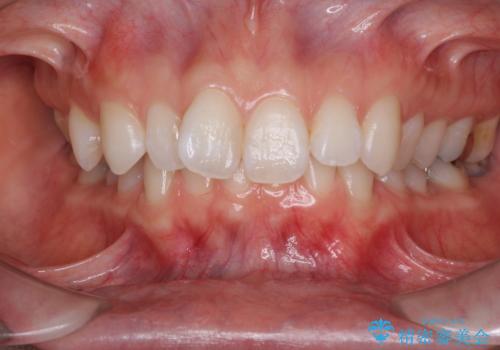

深い咬み合わせと奥歯のむし歯 総合歯科治療

- 奥歯の虫歯と前歯のデコボコや突出感を気にして来院された患者様です。

上顎歯列が、下顎に対して前方にありましたが、口元に出っ歯の印象がなかったため、親知らずを抜歯した上で、上顎歯列全体を後方に移動させることとしました。

矯正治療後は、奥歯の虫歯や銀歯を補綴・修復治療することとしました。